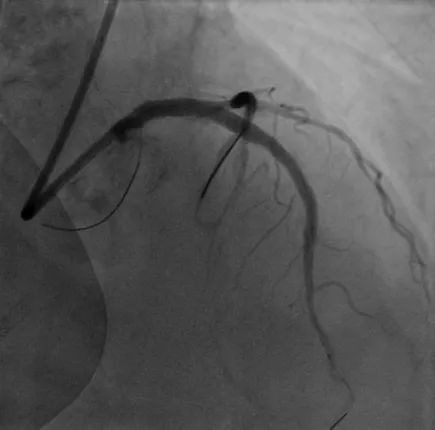

病例3

LM-LAD钙化病变:患者73岁女性,主因胸痛2小时入院,既往高血压病史,诊断不稳定型心绞痛。该患者1周前因心绞痛入院,CAG显示RCA95%狭窄伴血栓,于RCA植入一枚支架。患者左主干严重钙化病变狭窄80%,合并LAD弥漫钙化最重处狭窄90%,精准充分预处理格为重要,姚朱华主任团队综合评估患者病情后决定择期IVUS指导下行Shockwave冲击波球囊治疗。IVUS检查显示LM-LAD弥漫性钙化,最重处360°环形钙化,应用3.5*12mm Shockwave冲击波球囊顺利到达病变处,自LAD中段至LM末端连续释放脉冲,在左主干处释放4个周期(40个脉冲),成功于LM-LAD植入3枚支架,术后IVUS评估达到理想的支架膨胀及贴壁效果。

术前冠脉造影